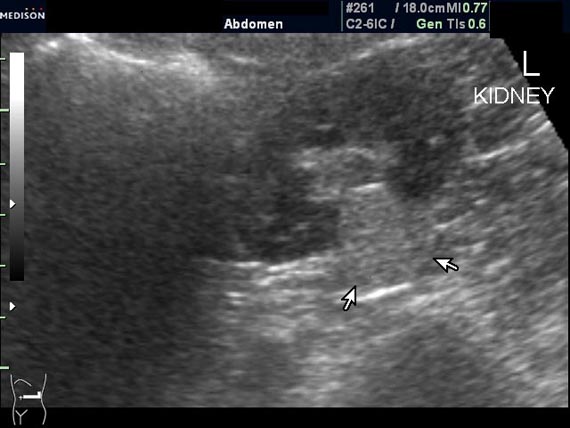

Женщина 50 лет. Жалоб нет. Обследование перед поездкой в санаторий по поводу дисфункции гепатобилиарной системы.

Случайная находка в нижней трети левой почки (не в полюсе, а по задне-медиальной поверхности).

ПО УЗ-семиотике образование соответствует ангиомиолипоме (AML). По правилам в таких случаях необходимо выполнить КТ, доказать преимущественно жировой состав опухоли, затем проводить УЗ-наблюдение.

Согласен. Именно с таким диагнозом (ангиомиолипома) отправил на КТ. Особенностью случая ИМХО является заметный "выход" образования за контур почки (на 2/3 объема).

При ультрасонографии ангиомиолипома выглядит как округлое образование без капсулы с однородной внутренней эхоструктурой и четкими контурами; эхогенность ее чаще всего равна или чуть выше эхогенности перинефральной клетчатки [7]. Значительно реже эхогенность ангиомиолипом может быть равна эхогенности почечной паренхимы; такие опухоли состоят почти полностью из гладкомышечной ткани [8]. Иногда позади ангиомиолипомы может определяться слабая акустическая тень.